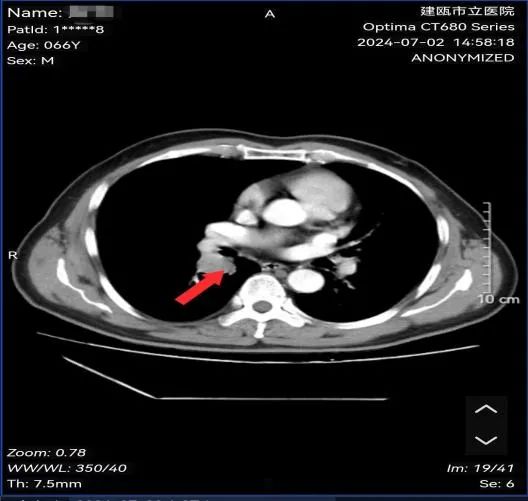

魏先生,男性,66岁,有长期吸烟史20余年,因反复咳嗽数月求诊我院,经肺部CT、支气管镜等检查确诊小细胞肺癌。经肺癌多学科诊疗小组专家会诊:建议完善骨ECT、脑部MRI检查后明确分期为:局限期小细胞肺癌,建议行同步放化疗治疗。

图为:治疗前病灶影像及病理结果